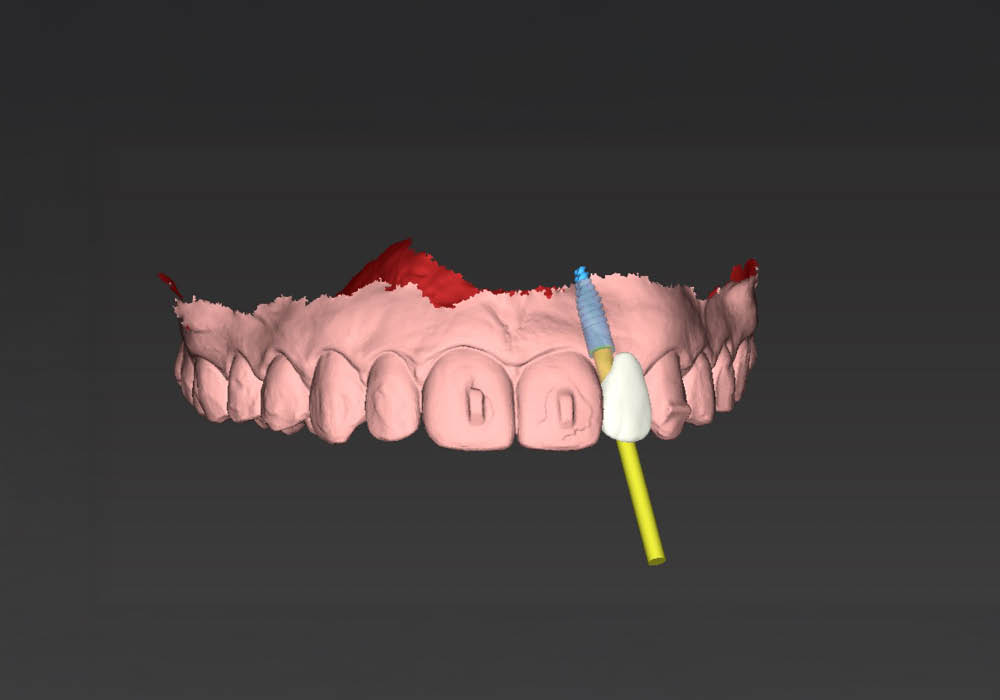

La pianificazione chirurgica ha previsto un’analisi tridimensionale dettagliata del sito implantare, valutato sia da angolazioni multiple sia in visione frontale diretta.

L’obiettivo era quello di definire con precisione posizione, profondità e inclinazione dell’impianto, tenendo conto della vicinanza delle radici adiacenti e della necessità di preservare un adeguato spessore vestibolare.

Questa fase ha permesso di anticipare eventuali criticità e assicurare l’inserzione corretta all’interno dei limiti anatomici disponibili.

4. Esportazione dei file STL

Una volta confermata la posizione implantare, i file sono stati esportati in formato STL per le successive fasi di modellazione e costruzione dei dispositivi ausiliari.

5. Costruzione del tappo di guarigione in PEEK

Su misura per la paziente, è stato realizzato un tappo di guarigione anatomico in PEEK, progettato per guidare correttamente la guarigione dei tessuti molli e mantenere il profilo di emergenza ideale in funzione del futuro restauro.